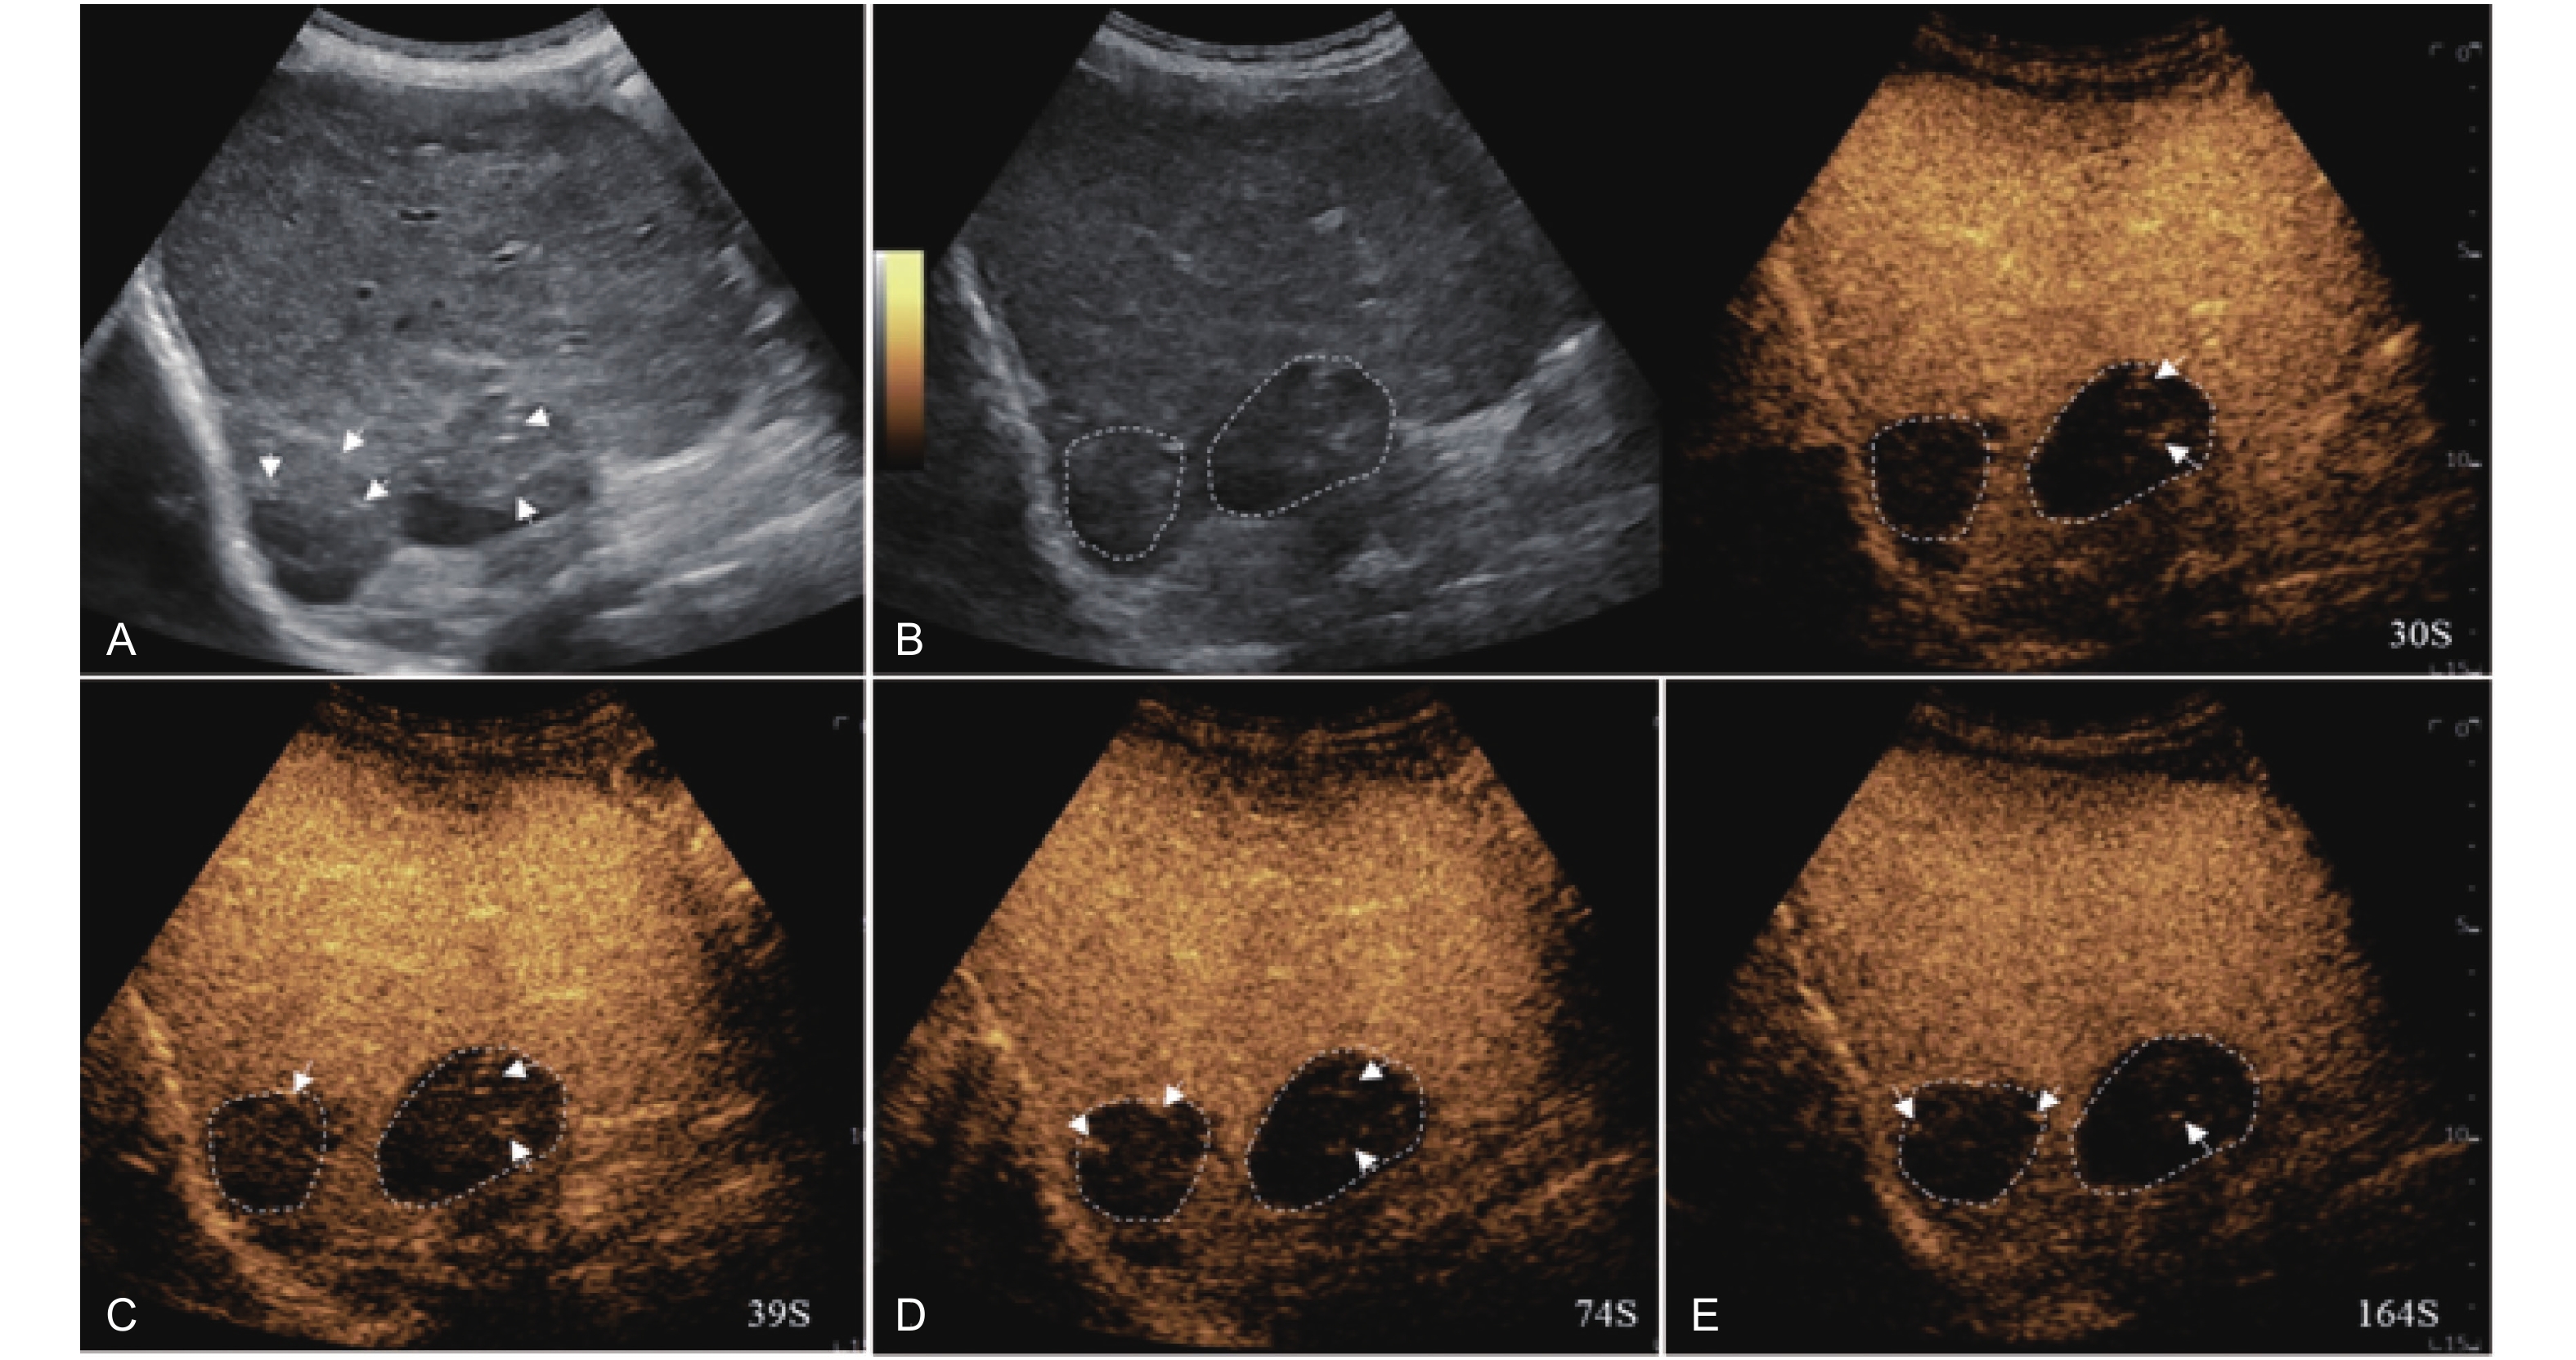

Figure 4

LR-TR Nonviable. Example of a nonviable tumor 14 days after TACE. (A) B-mode image shows two heterogeneous hyperechoic lesions (thick arrow) with irregular shape, measuring 17 mm and 18 mm in segment VI; (B-E) CEUS shows no intralesional enhancement with perilesional enhancement identical to the surrounding liver parenchyma in all phases. Findings are consistent with LR-TR Nonviable."